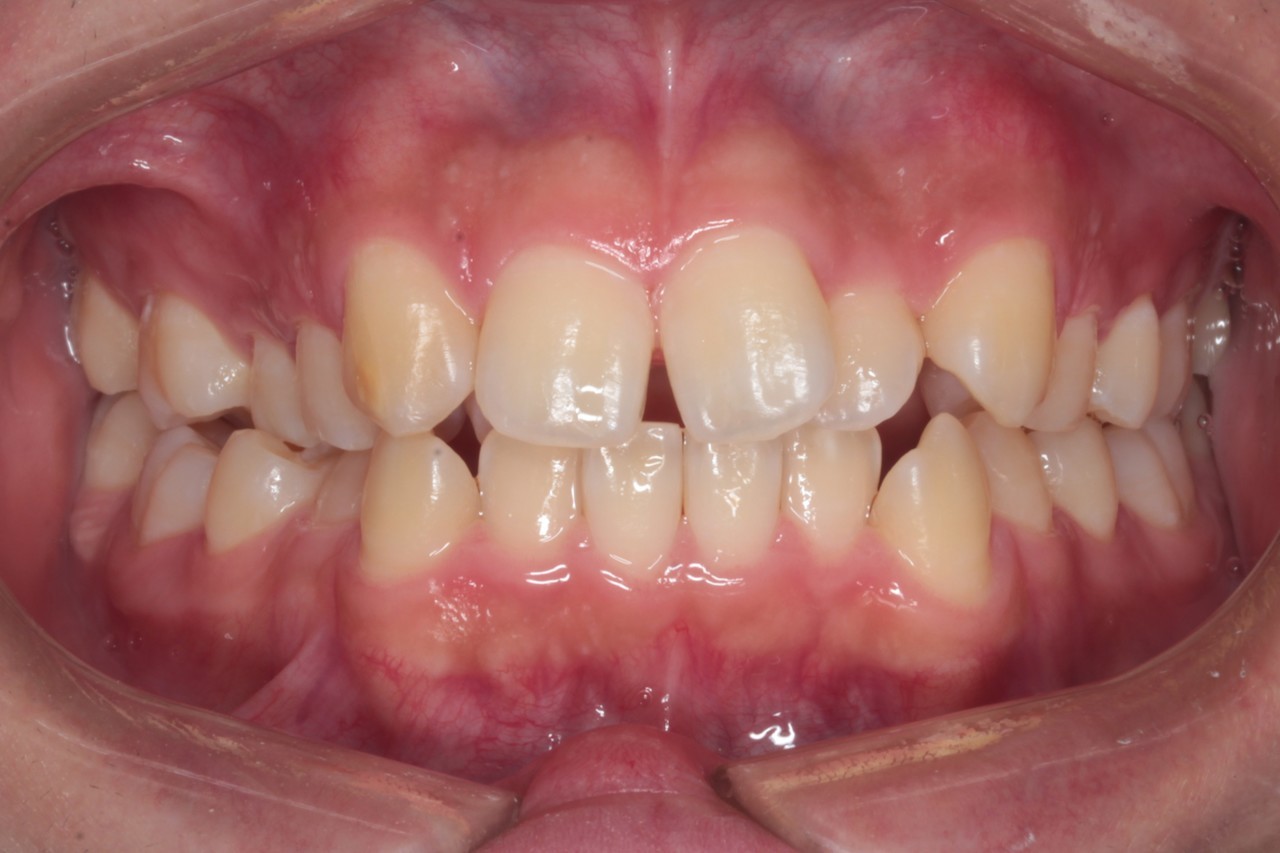

治療前

『交叉咬合(こうさこうごう)』は

上下の歯の関係が一部反対になっている状態の歯並びです

クロスバイトとも呼ばれます 今回は右の5番目あたり(向かって左側)に起きています

『叢生(そうせい)』は

草むらを表す『叢(そう)』のように込み入った歯並びを指します

日本人に多い、前歯がデコボコした歯並びです

調布市の20代男性

主訴:歯並びをきれいにしたい

使用装置:インビザライン

治療期間:約3年

治療費用:93.5万円(税込)

治療結果:交叉咬合と叢生が改善されました

このレベルの叢生であれば、誰しも抜歯矯正を考えると思います

しかし今回は、抜歯矯正を行うと後のかみ合わせなどのリスクが高く感じたため

親知らずの抜歯にとどめ、奥歯をそのスペースに送ることで

前歯が収まるスペースを得ることを考えました